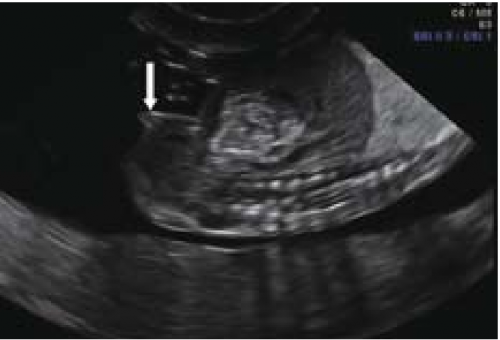

sagittal sign שתואר לראשונה על ידי Emerson וחב'[4] הוא הסמן הסונוגרפי המקובל ביותר לקביעת מין העובר בשלבי ההיריון המוקדמים. העובר נסרק בחתכים סגיטליים בקו האמצע. באזור העכוז הנסרק בחתך זה, ניתן לזהות בליטה שמייצגת את הדגדגן או את איבר המין הזכרי. כאשר כיוון הבליטה כלפי מעלה, מין העובר זכר (תמונה 1) וכיוון כלפי מטה מבטא מין נקבה (תמונה 2). שימוש בסמן סונוגרפי זה אפשר לזהות מין העובר ב-71 אחוז (5\7) מהעוברים בשבוע 10 עד 11.9, אך האבחנה היתה נכונה ב-60 אחוז (3\5) בלבד. דיוק האבחנה עלה עם התקדמות גיל ההיריון ל-75 אחוז, 100 אחוז, 98 אחוז ו-100 אחוז בשבועות 12-13.9, 14-15.9, 16-17.0 ו-18-20.4, בהתאמה[4]. דיווחים רבים אחרים דיווחו על אבחון מין העובר בסוף הטרימסטר הראשון ותחילת השני (14-4) (ראו טבלה 1).

ברונשטיין וחב׳[7] דיווחו שדיוק אבחון מין העובר על ידי אולטרסאונד נרתיקי עולה עם הניסיון, כך שבשנתיים הראשונות לשימוש באולטרסאונד נרתיקי, המין אובחן בדיוק של 76 אחוז ועלה ל-80 אחוז בשנתיים לאחר מכן בין השבועות 14-13 להיריון, ובשבוע 16-15 הדיוק עלה מ-88 אחוז בשנתיים הראשונות לנסיונם ל-96.7 אחוז בשנתיים לאחר מכן. בעבודה זו, מין זכר נקבע על סמך הדגמת מבנה דמוי כיפה (dome sign) המייצג שק אשכים (תמונה 3) בעוד מין נקבה נקבע על סמך הדגמת שניים או ארבעה קווים מקבילים (parallel lines) המייצגים את השפתיים הקטנות והגדולות (תמונה 4) . סימנים סונוגרפיים נוספים בעבודה זו[7] היו הדגמת קו אקוגיני הנמשך מבסיס ועד קצה איבר המין הזכרי ומייצג קו האמצע של הפניס (תמונה 5) וכיוון הפאלוס העוברי (כלפי מעלה מייצג זכר וכלפי מטה נקבה).